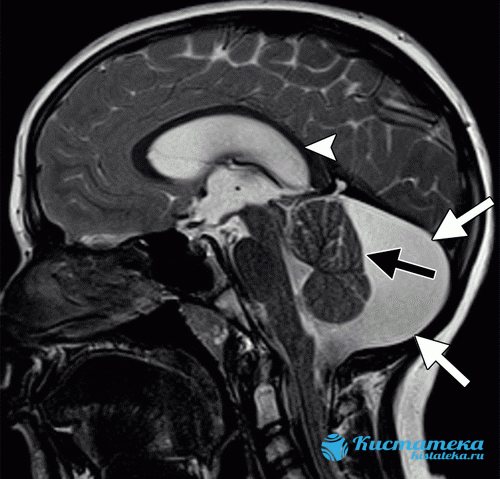

На изображении показана ретроцебеллярная

арахноидальная киста

с явным увеличением задней ямки (белые стрелки).